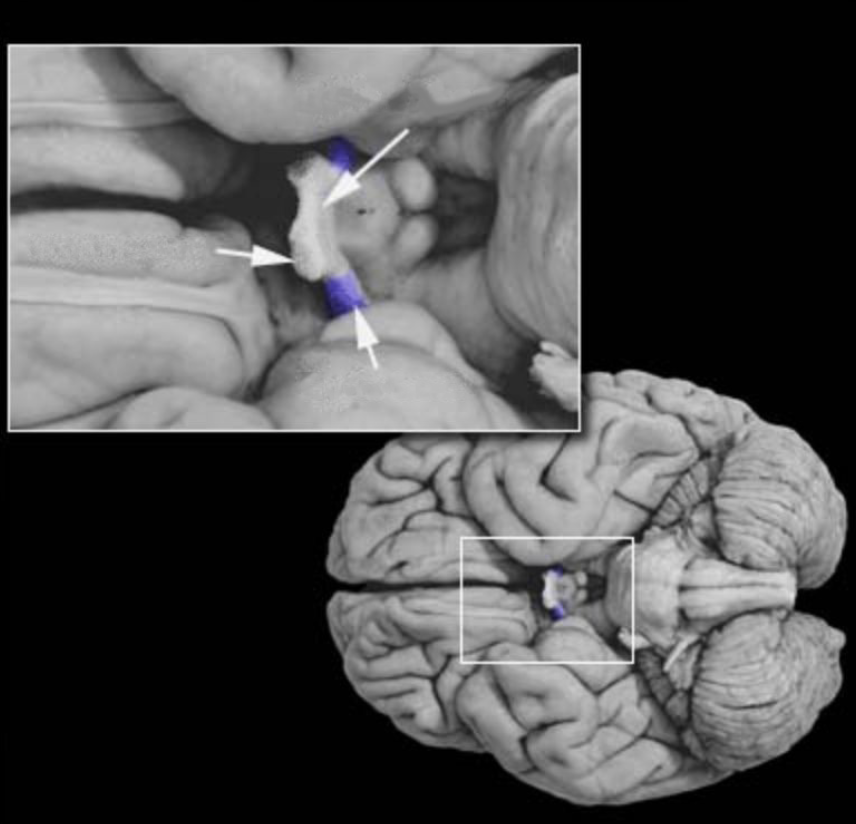

Cerebral peduncles

Three major white matter structures that contain efferent and afferent axons of the cerebellum (peduncle means stalk). These three peduncles are named the inferior, middle, and superior cerebellar peduncles.

Cerebellum

Prominent convoluted hindbrain structure (Latin for "little brain") consisting of a three-layered cortex, subcortical white matter, deep nuclei, and three peduncles that connect the cerebellum and brainstem. The cerebellum is concerned with the coordination of ongoing movement, motor planning, and motor learning; it also plays a role in coordinating and sequencing cognitive processing.

Cerebellar peduncles (superior, middle, inferior)

Three major white matter structures that contain efferent and afferent axons of the cerebellum (peduncle means stalk). These three peduncles are named the inferior, middle, and superior cerebellar peduncles. Prominent structures (peduncle means "stalk") observed on the ventral surface of the midbrain comprising the tegmentum and the more ventrally located white matter tracts (basis pedunculi). In common usage, the term cerebral peduncle denotes these white matter tracts, which contain the efferent axons of the cerebral cortex that project to the brainstem and spinal cord.